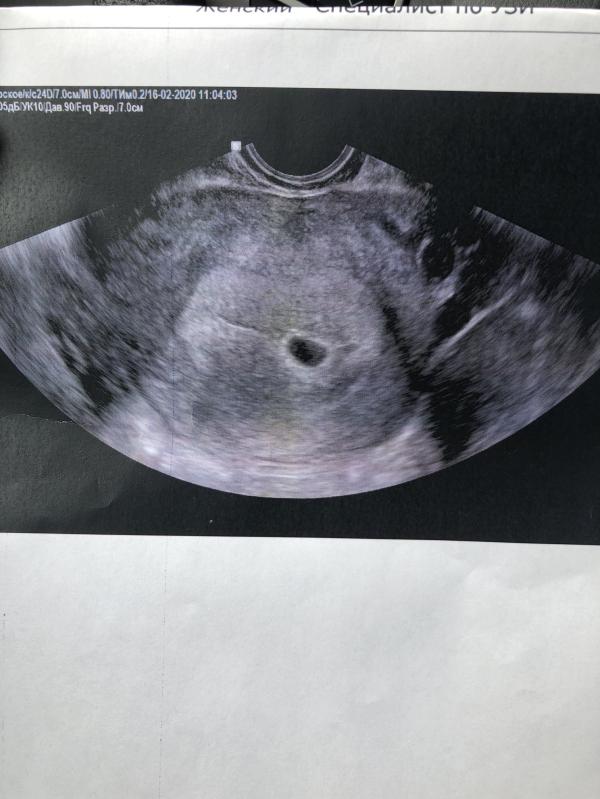

Пошла на УЗИ. Срок 5 недель.

Эмбрион пока 🙏🏻 не увидели.

ХГЧ 15520